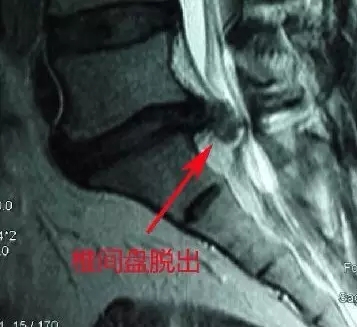

(磁共振和CT椎间盘脱出)

(椎间盘脱出)